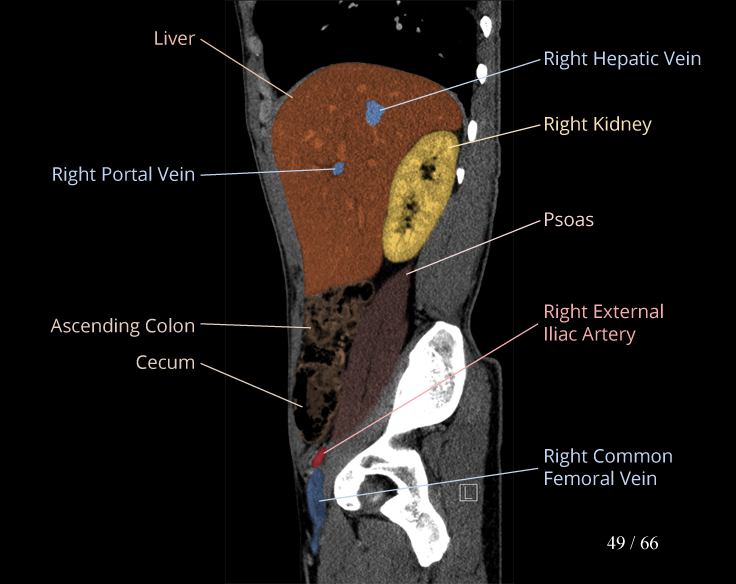

Body

Covers abdominal CT anatomy.